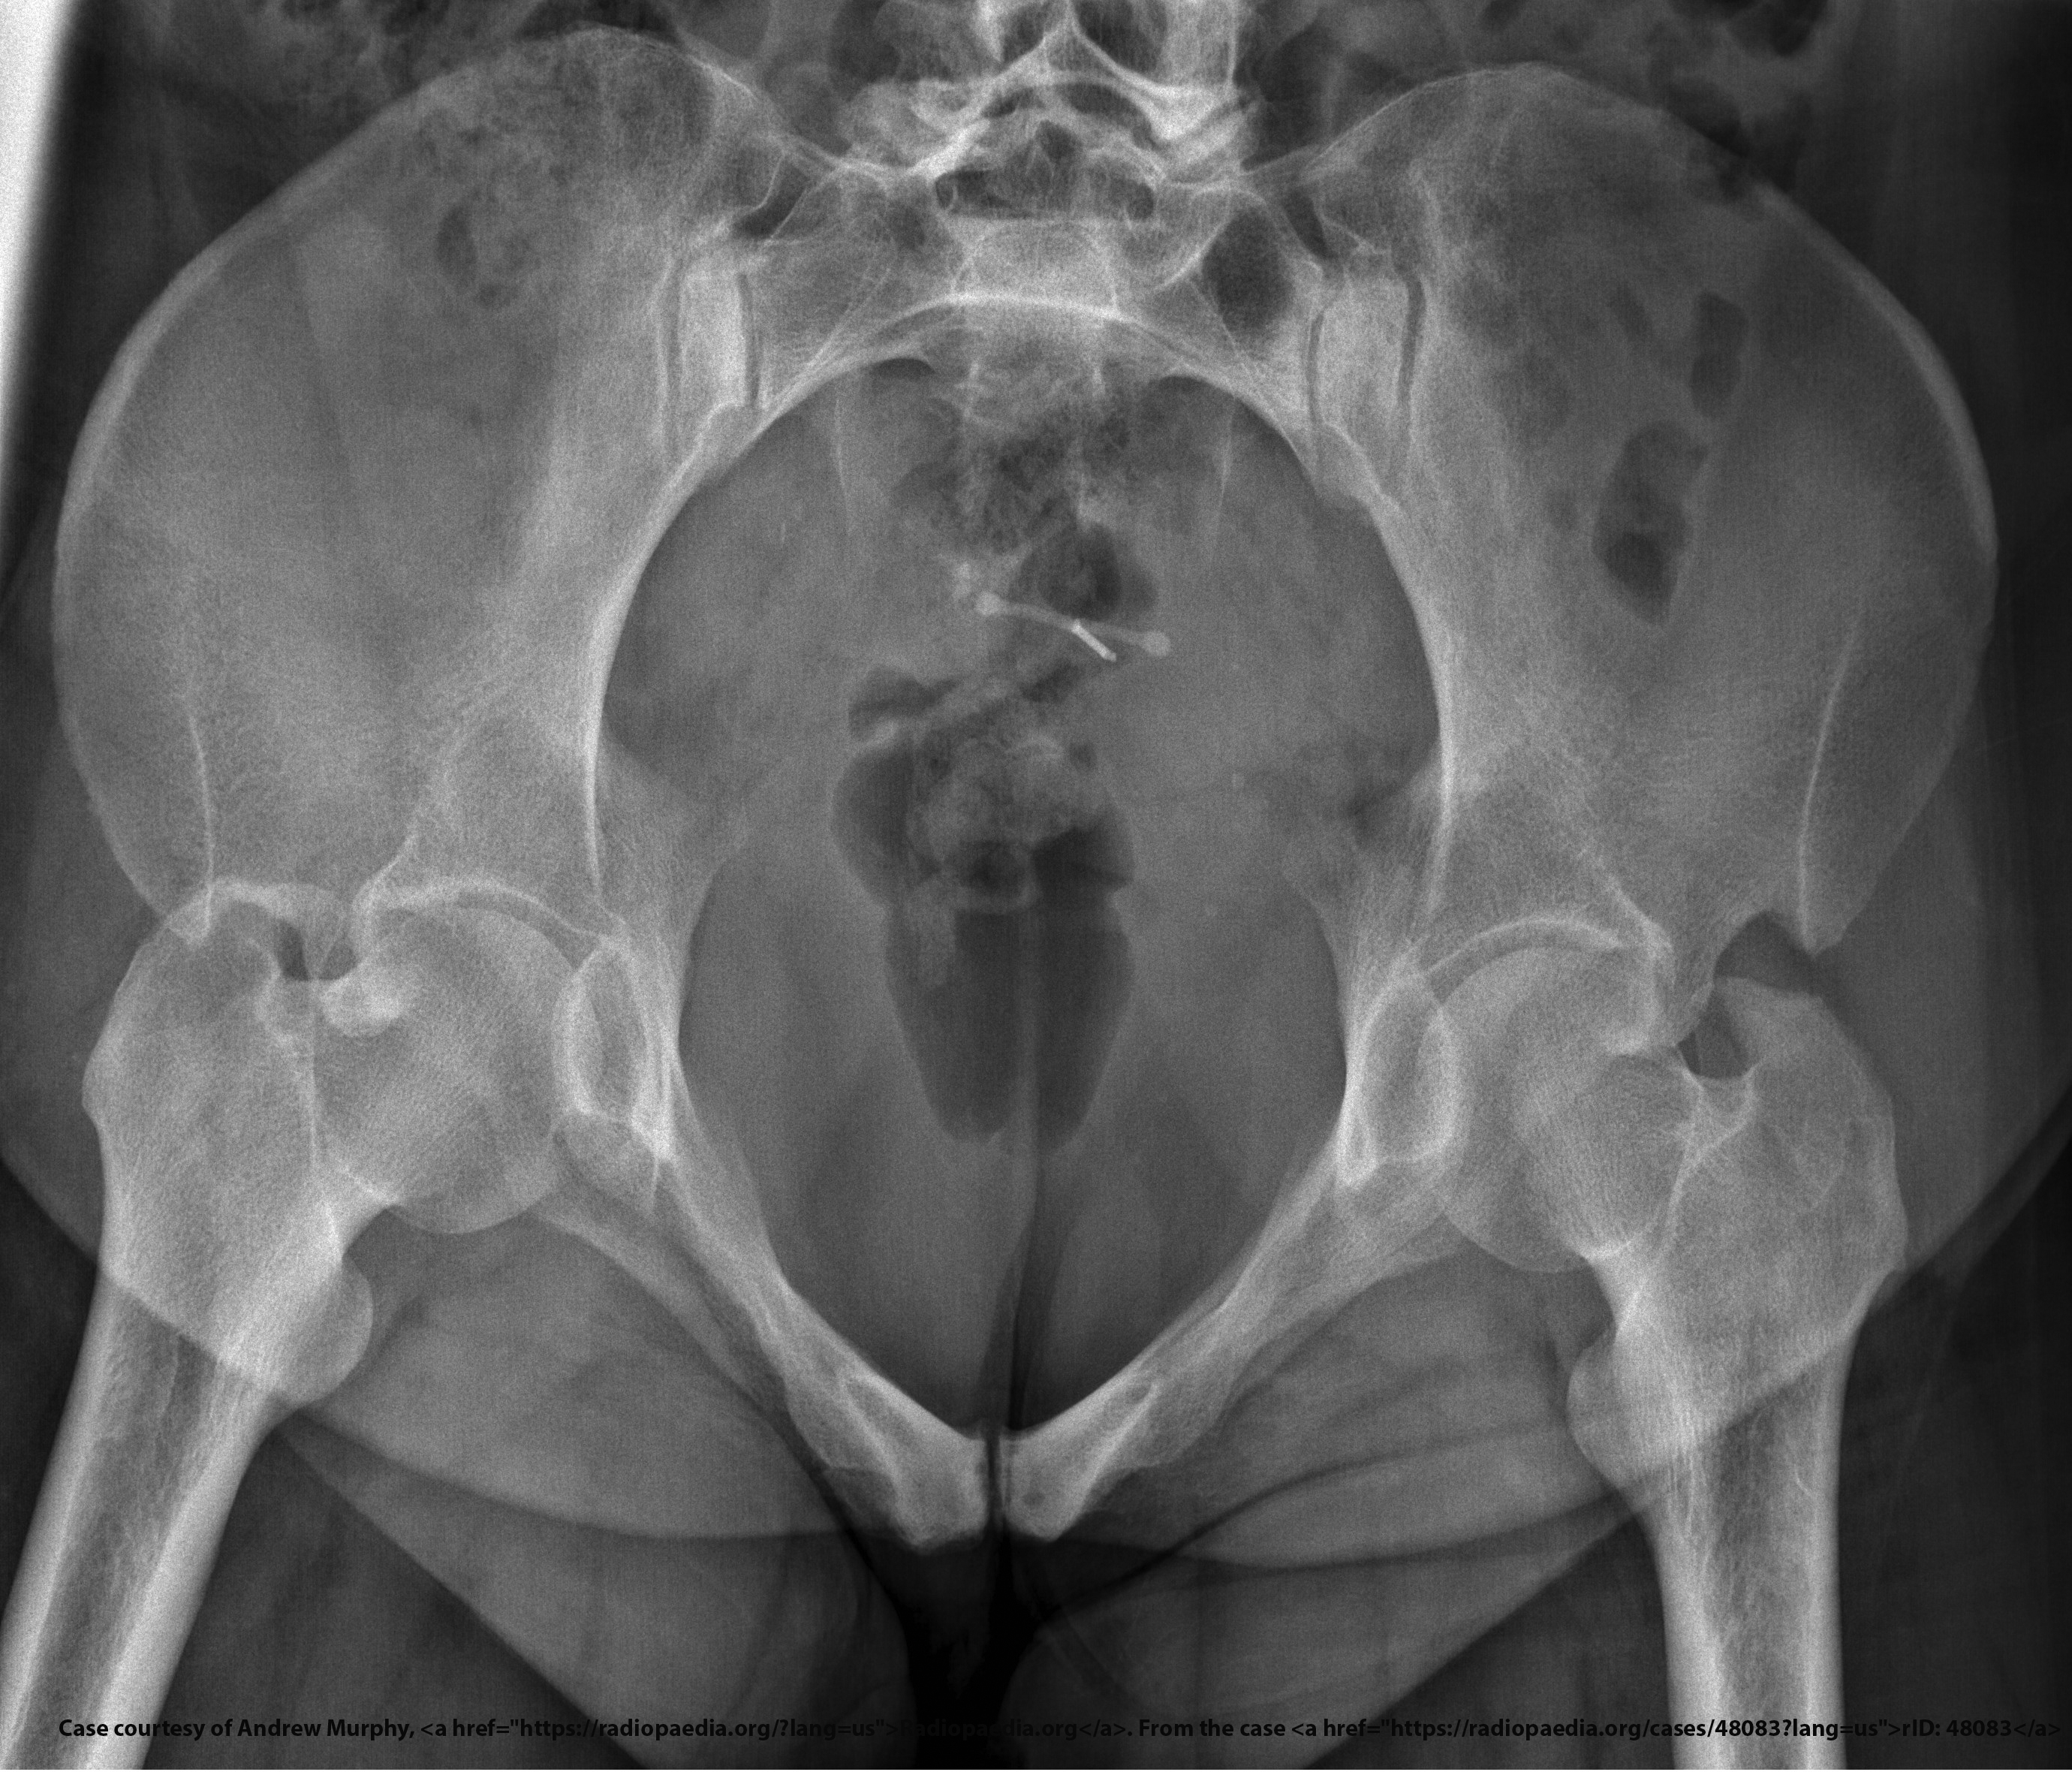

<p>What do inlet and outlet views evaluate?</p>

What do inlet and outlet views evaluate?

Pelvic fracture displacement and stability.

What anatomical structures does the inlet projection demonstrate?

Pelvic brim, anterior pelvis, acetabulum.

<p>Pelvic brim, anterior pelvis, acetabulum.</p>